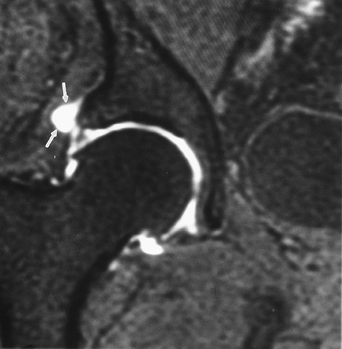

![]() |

FIGURE 4-30 Coronal MR arthrogram image with superior labral tear and paralabral cyst (arrows).

Trauma: Soft Tissue Trauma: Acetabular Labral Tears

The labrum attaches to the acetabular

Labral detachments and tears occur. Lesions are most common in the superior and anterior quadrants.

Labral tears, especially detachments, may be associated with paralabral cysts.

MR arthrography is the technique of choice for labral evaluation.